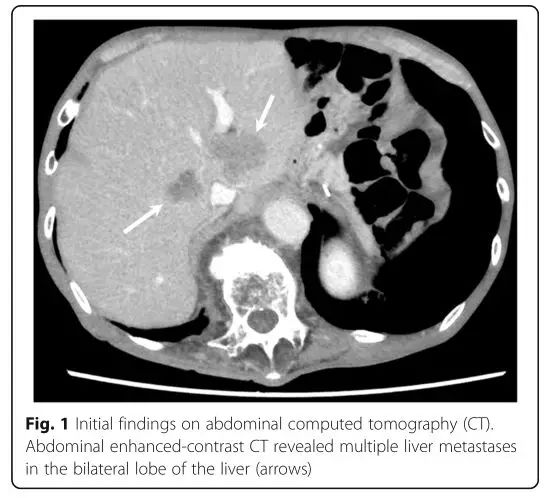

1名77歲的日本男子初診胃癌后,接受了腹腔鏡全胃切除術(shù)和淋巴結(jié)清掃術(shù)。首次手術(shù)的28個月后,腹部CT顯示脾轉(zhuǎn)移,遂行脾切除術(shù)。此后該患者進行了S-1聯(lián)合奧沙利鉑治療,4個月CT復(fù)查提示肝內(nèi)多發(fā)轉(zhuǎn)移灶。后經(jīng)二線治療(雷莫蘆單抗+紫杉醇)后,腹部CT顯示肝轉(zhuǎn)移灶進展。

最終,患者的三線治療選擇了O藥。4個周期治療后,肝轉(zhuǎn)移灶明顯縮小,病灶較基線水平縮小55%,療效達(dá)到部分緩解。8個周期后,病灶縮小了82.6%。12個周期后,腹部CT顯示所有靶病灶全部消失,療效評估為完全緩解。治療過程中,患者沒有出現(xiàn)任何不良反應(yīng)(包括免疫相關(guān)不良反應(yīng))。患者繼續(xù)使用O藥治療,用藥8個月無疾病復(fù)發(fā)跡象。